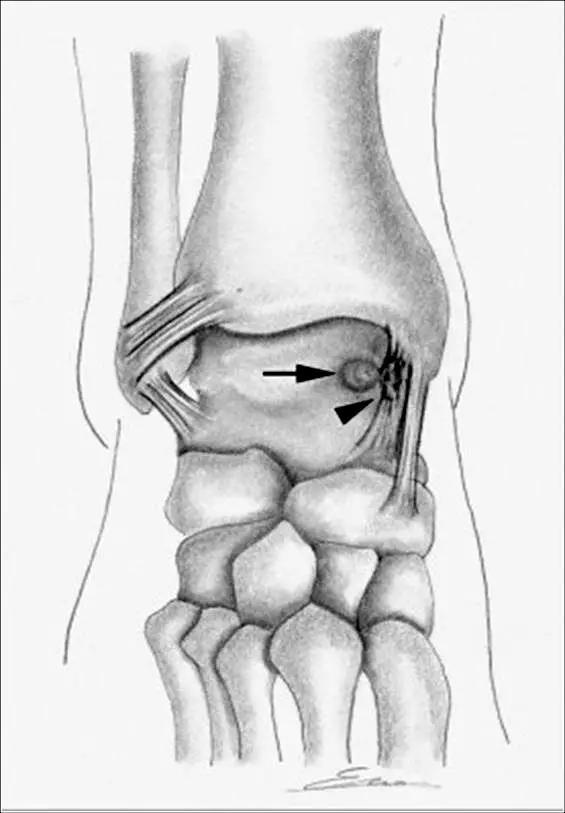

5.后内侧撞击综合症:

影像学表现为距骨胫骨间肌腱及趾长屈肌腱水肿、增厚,内踝及距骨后内侧骨赘形成。

轴位示意图示后内侧撞击综合征:M:内踝;L:外踝;TP:胫后肌腱;FDL:趾长屈肌腱;Talus:距骨。短箭:距骨胫骨间肌腱深层纤维;箭头:距骨胫骨间肌腱后部纤维。

X线平片示胫骨后部骨赘形成,MR质子像黑箭示胫骨内后侧骨赘形成,白箭示内后侧软组织增厚, 白箭头:胫后肌腱;黑箭头:趾长屈肌腱